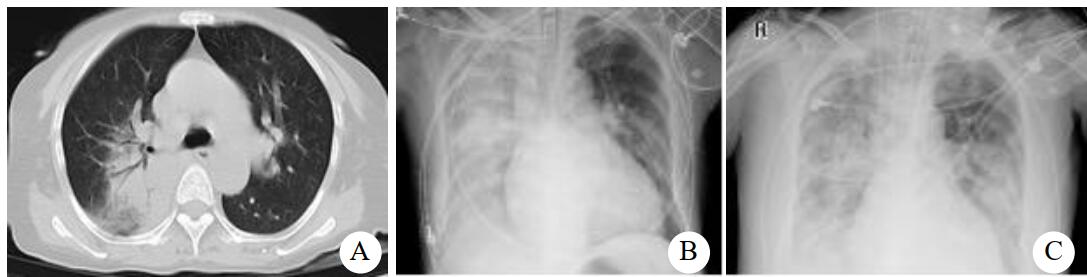

病例2,女,55岁,有鸽子喂养史,近半个月来咳嗽发热,咳剧时伴胸闷气喘,活动后加重,近1周出现纳差,伴呕吐、腹泻。入院查体:体温38 ℃,脉搏126次/min,呼吸32次/min,血压91/48 mmHg。神清,无皮疹,浅表淋巴结无肿大,右肺闻及湿啰音,心律齐,未闻及杂音,肝脾肋下未触及。胸部CT示右肺大片实变,见图 3A。甲、乙型流感抗原检测阴性。入院诊断:重症社区获得性肺炎。予无创机械通气,美罗培南+莫西沙星抗感染,奥司他韦抗病毒,入院第3天查胸片示两肺斑片状模糊影(图 3B),予气管插管辅助通气,查PCT 7.88 ng/mL。改用阿奇霉素+万古霉素抗感染。入院第8天行肺泡灌洗液mNGS检测:鹦鹉热衣原体(序列数314),鲍曼不动杆菌(序列数23),改舒普深+替加环素治疗。经治疗后,患者症状无明显好转,并发严重上消化道出血,入院第13天查胸片示病灶范围扩大(见图 3C),因病情危重,生命体征不平稳未行CT复查,患者病情进行性恶化,治疗14 d后死亡。

| A:入院时胸部CT,右肺大片实变;B:入院第3天床边胸片,两肺斑片状模糊影;C:入院第13天床边胸片,两肺斑片状模糊影,较前有进展 图 3 病例2胸部检查结果 |